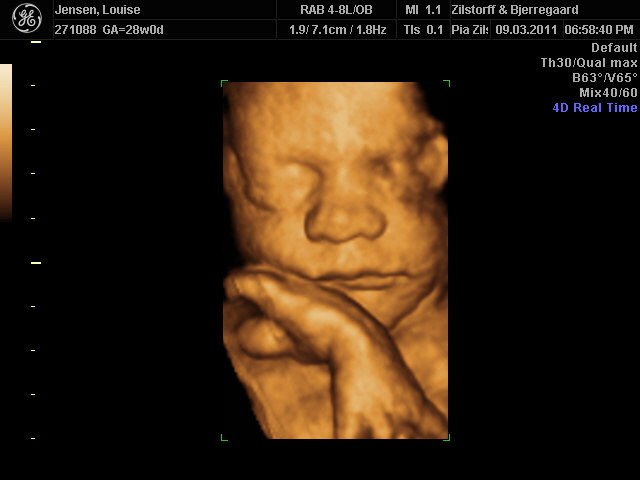

Jeg og kæresten var til 3D-scanning igår - sikke da en oplevelse  - det er da helt klart alle pengene værd ..

Hold da op en smækker lækker baby'boy der gemmer sig derinde i hulen, fy føj mor her fik tårere i øjne .. sikke da alt den kærliighed der væltede over mig .. suk suk

han ligner han far meget  - det er så vidunderligt hvad man dog kan se..

perfekt hjertelyd og vægten siger 1166 og er i uge 29 nu

Vedhæftede fotos (klik for at se i fuld størrelse)